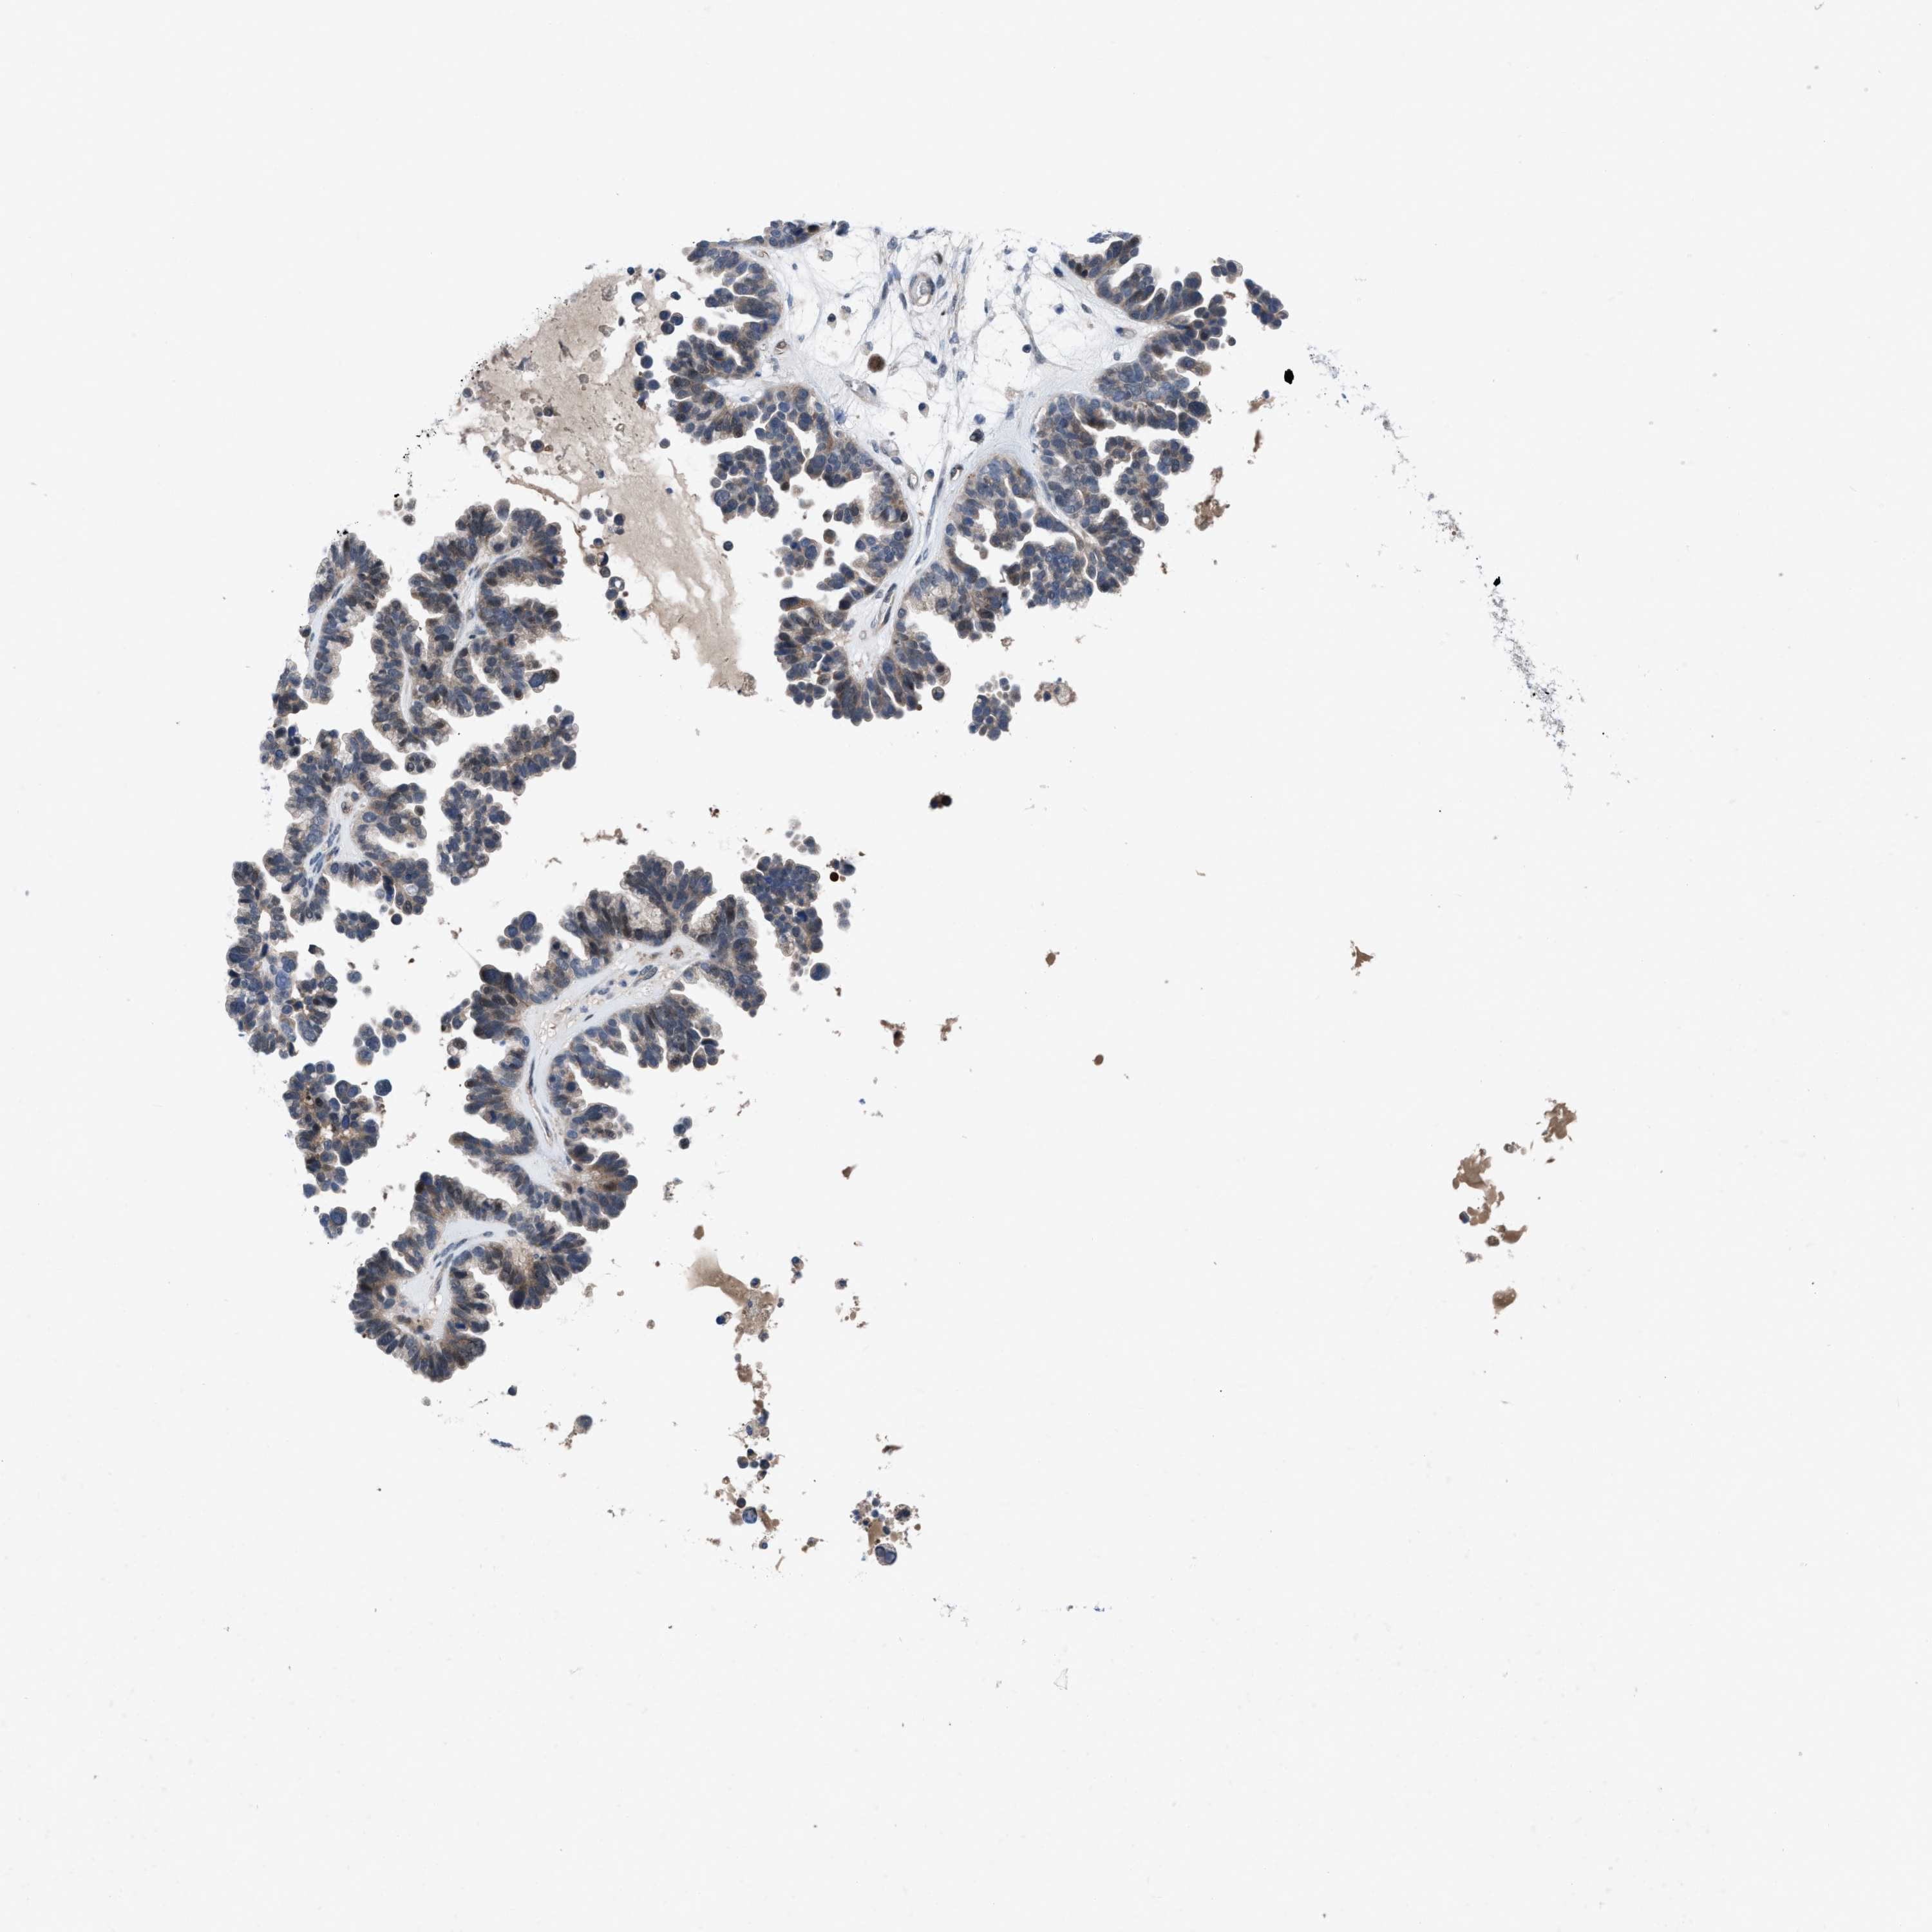

OVARIAN CANCER - Protein expressioni

A mouse-over function shows sample information and annotation data. Click on an image to view it in a full screen mode. Samples can be filtered based on level of antibody staining by selecting one or several of the following categories: high, medium, low and not detected. The assay and annotation is described here.

Note that samples used for immunohistochemistry by the Human Protein Atlas do not correspond to samples in the TCGA dataset.

Antibody stainingi

Antibody staining in the annotated cell types in the current human tissue is reported as not detected, low, medium, or high, based on conventional immunohistochemistry profiling in selected tissues. This score is based on the combination of the staining intensity and fraction of stained cells.

Each image is clickable and will lead to virtual microscopy that enables deeper exploration of all samples and also displays staining intensity scores, fraction scores and subcellular localization as well as patient and tissue information for each sample.

Antibody HPA019011

Staining

High

Medium

Low

Not detected

Intensity

Strong

Moderate

Weak

Negative

Quantity

>75%

75%-25%

<25%

None

Location

Nuclear

Cytoplasmic/membranous

Cytoplasmic/membranous,nuclear

Cystadenocarcinoma, serous, NOS

Carcinoma, endometroid

Cystadenocarcinoma, mucinous, NOS

Carcinoma, NOS